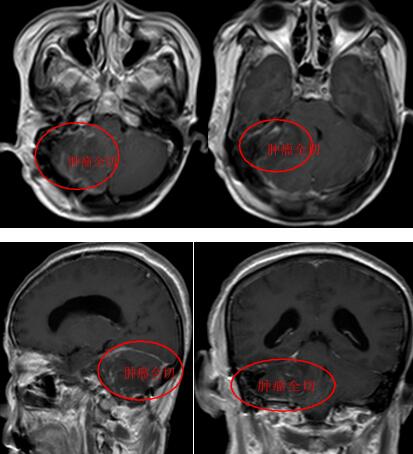

在完善术前准备并对手术方案进行认真论证后,神经外十科医疗团队采取右侧颞下联合乙状窦后入路的方式,行右侧幕下岩斜区脑膜瘤切除术。手术的难点在于肿瘤显露困难,它位于脑子底部正中间,起源于双侧三叉神经内侧、面神经内侧、上中斜坡上缘、上斜坡下缘到中斜坡的下缘,稍有差池便会损伤颅神经、脑血管。术中,在显微镜下,医生凭借精湛的手术技巧和丰富的临床经验对肿瘤进行精细剥离,肿瘤全切。

术后,杨阿姨神志清醒,因术中各组颅神经保护良好,无明显颅神经损伤的阳性体征表现,肢体活动情况好,面部及吞咽功能完好。